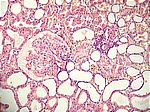

Schockniere, HE